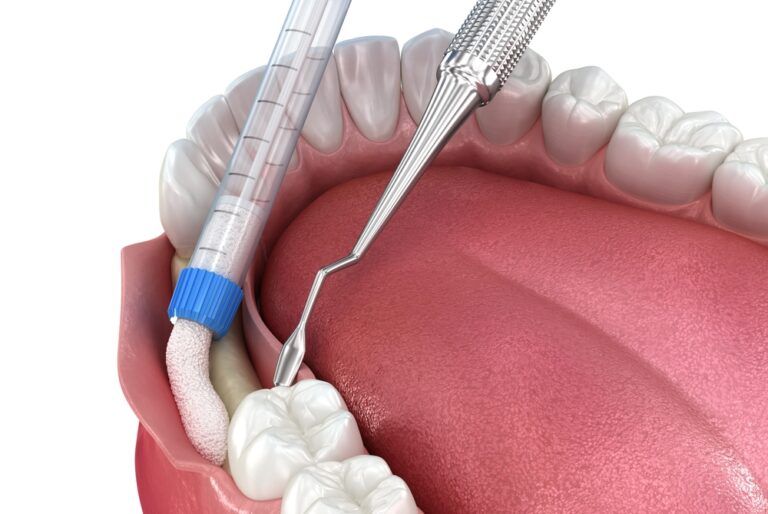

Bone Grafting for Dental Implants: Why It’s Needed

Dental implants have become the gold standard for replacing missing teeth, offering long-term stability, natural function, and a lifelike appearance. However, not every patient is immediately ready for implant placement, especially those who have experienced significant jawbone loss. In such